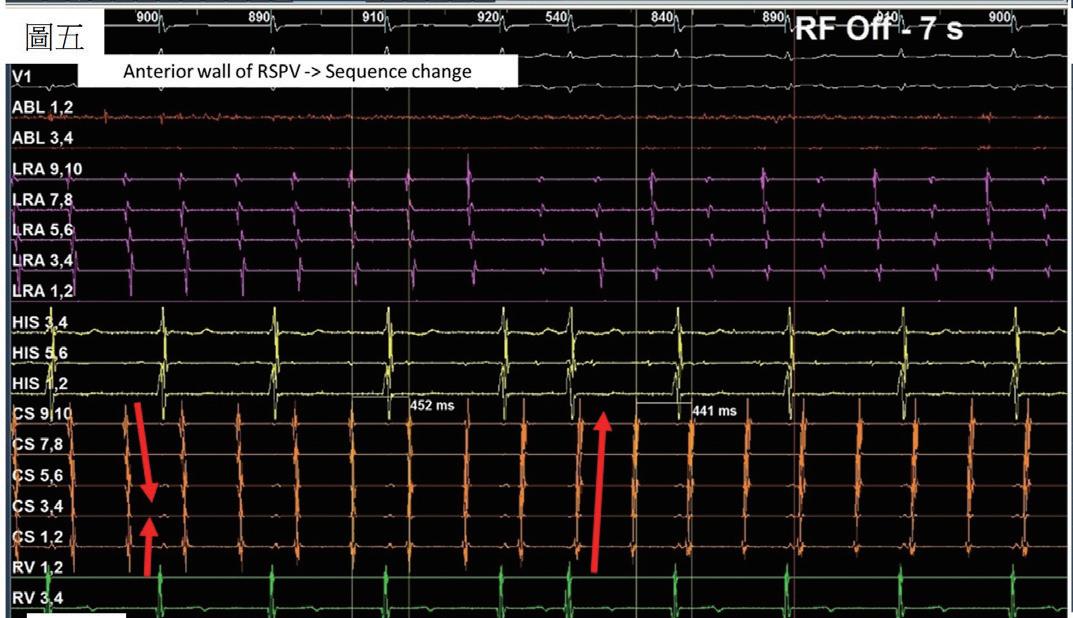

(圖五)、 Mapping後判斷可能之critical isthmus位 於right superior pulmonary vein開口之後 側與前側。針對這兩個位置電燒後,發 生第二次訊號序列變換,轉變為CS 1,2往 CS 9,10之走向。

(圖四)、 病人接受cavo-tricuspid isthmus阻斷後發生 第一次sequence change。病人在CS的訊號序 列呈現“reverse chevron pattern”。而且右 心房無法順利 entrainment 。於是進行心房 中膈穿刺,前往左心房繼續治療心房撲動。